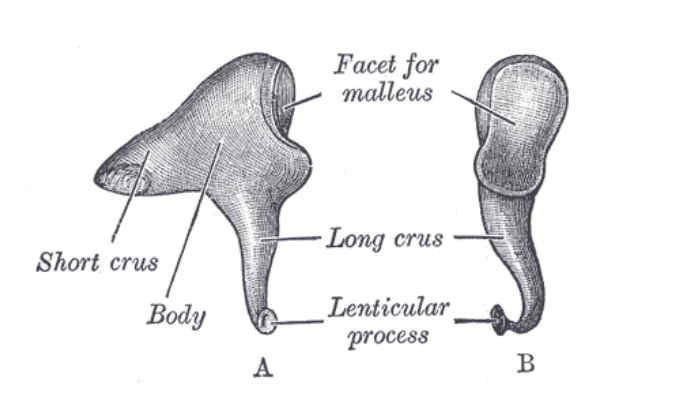

The Incus

The Incus

Body of the incus

Short crus of the incus

Long crus of the incus